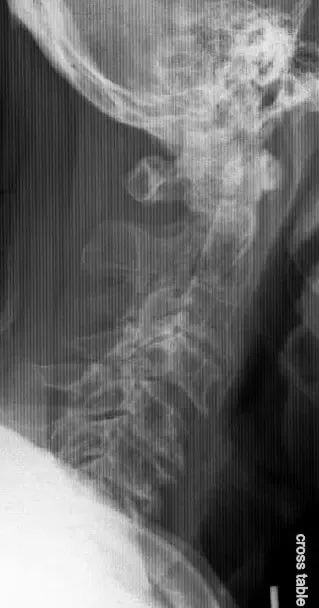

Radiografías Vista lateral de la columna cervical que muestra enfermedad degenerativa avanzada de la columna cervical